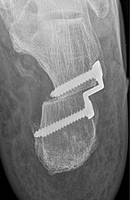

Der Knick-Senkfuß beim Erwachsenen entwickelt sich in der Regel durch eine schmerzhafte Insuffizienz der M. Tibialis posterior Sehne. Die Sehne verläuft an der Innenseite unter den Fuß und stützt das Fußlängsgewölbe ab. Sie sorgt beim Gehen für die notwendige Stabilität um sich richtig abstoßen zu können. Insbesondere Übergewicht und Verschleiß dieser Sehne führen zum Bild der klassischen Knick-Senkfußdeformität. Es kommt zu kleinen Teileinrissen auf dem Boden einer chronischen Tendinitis (Sehnenentzündung) oder Tenosynovitis (Sehnenschleimhautentzündung).

Ein akutes Trauma mit kompletten Riss der Sehne mit nachfolgendem Kraftverlust sind die Ausnahme.

Abb.1: Die MRT zeigt eine chronische Entzündung der Sehne mit Erguss (Pfeil).